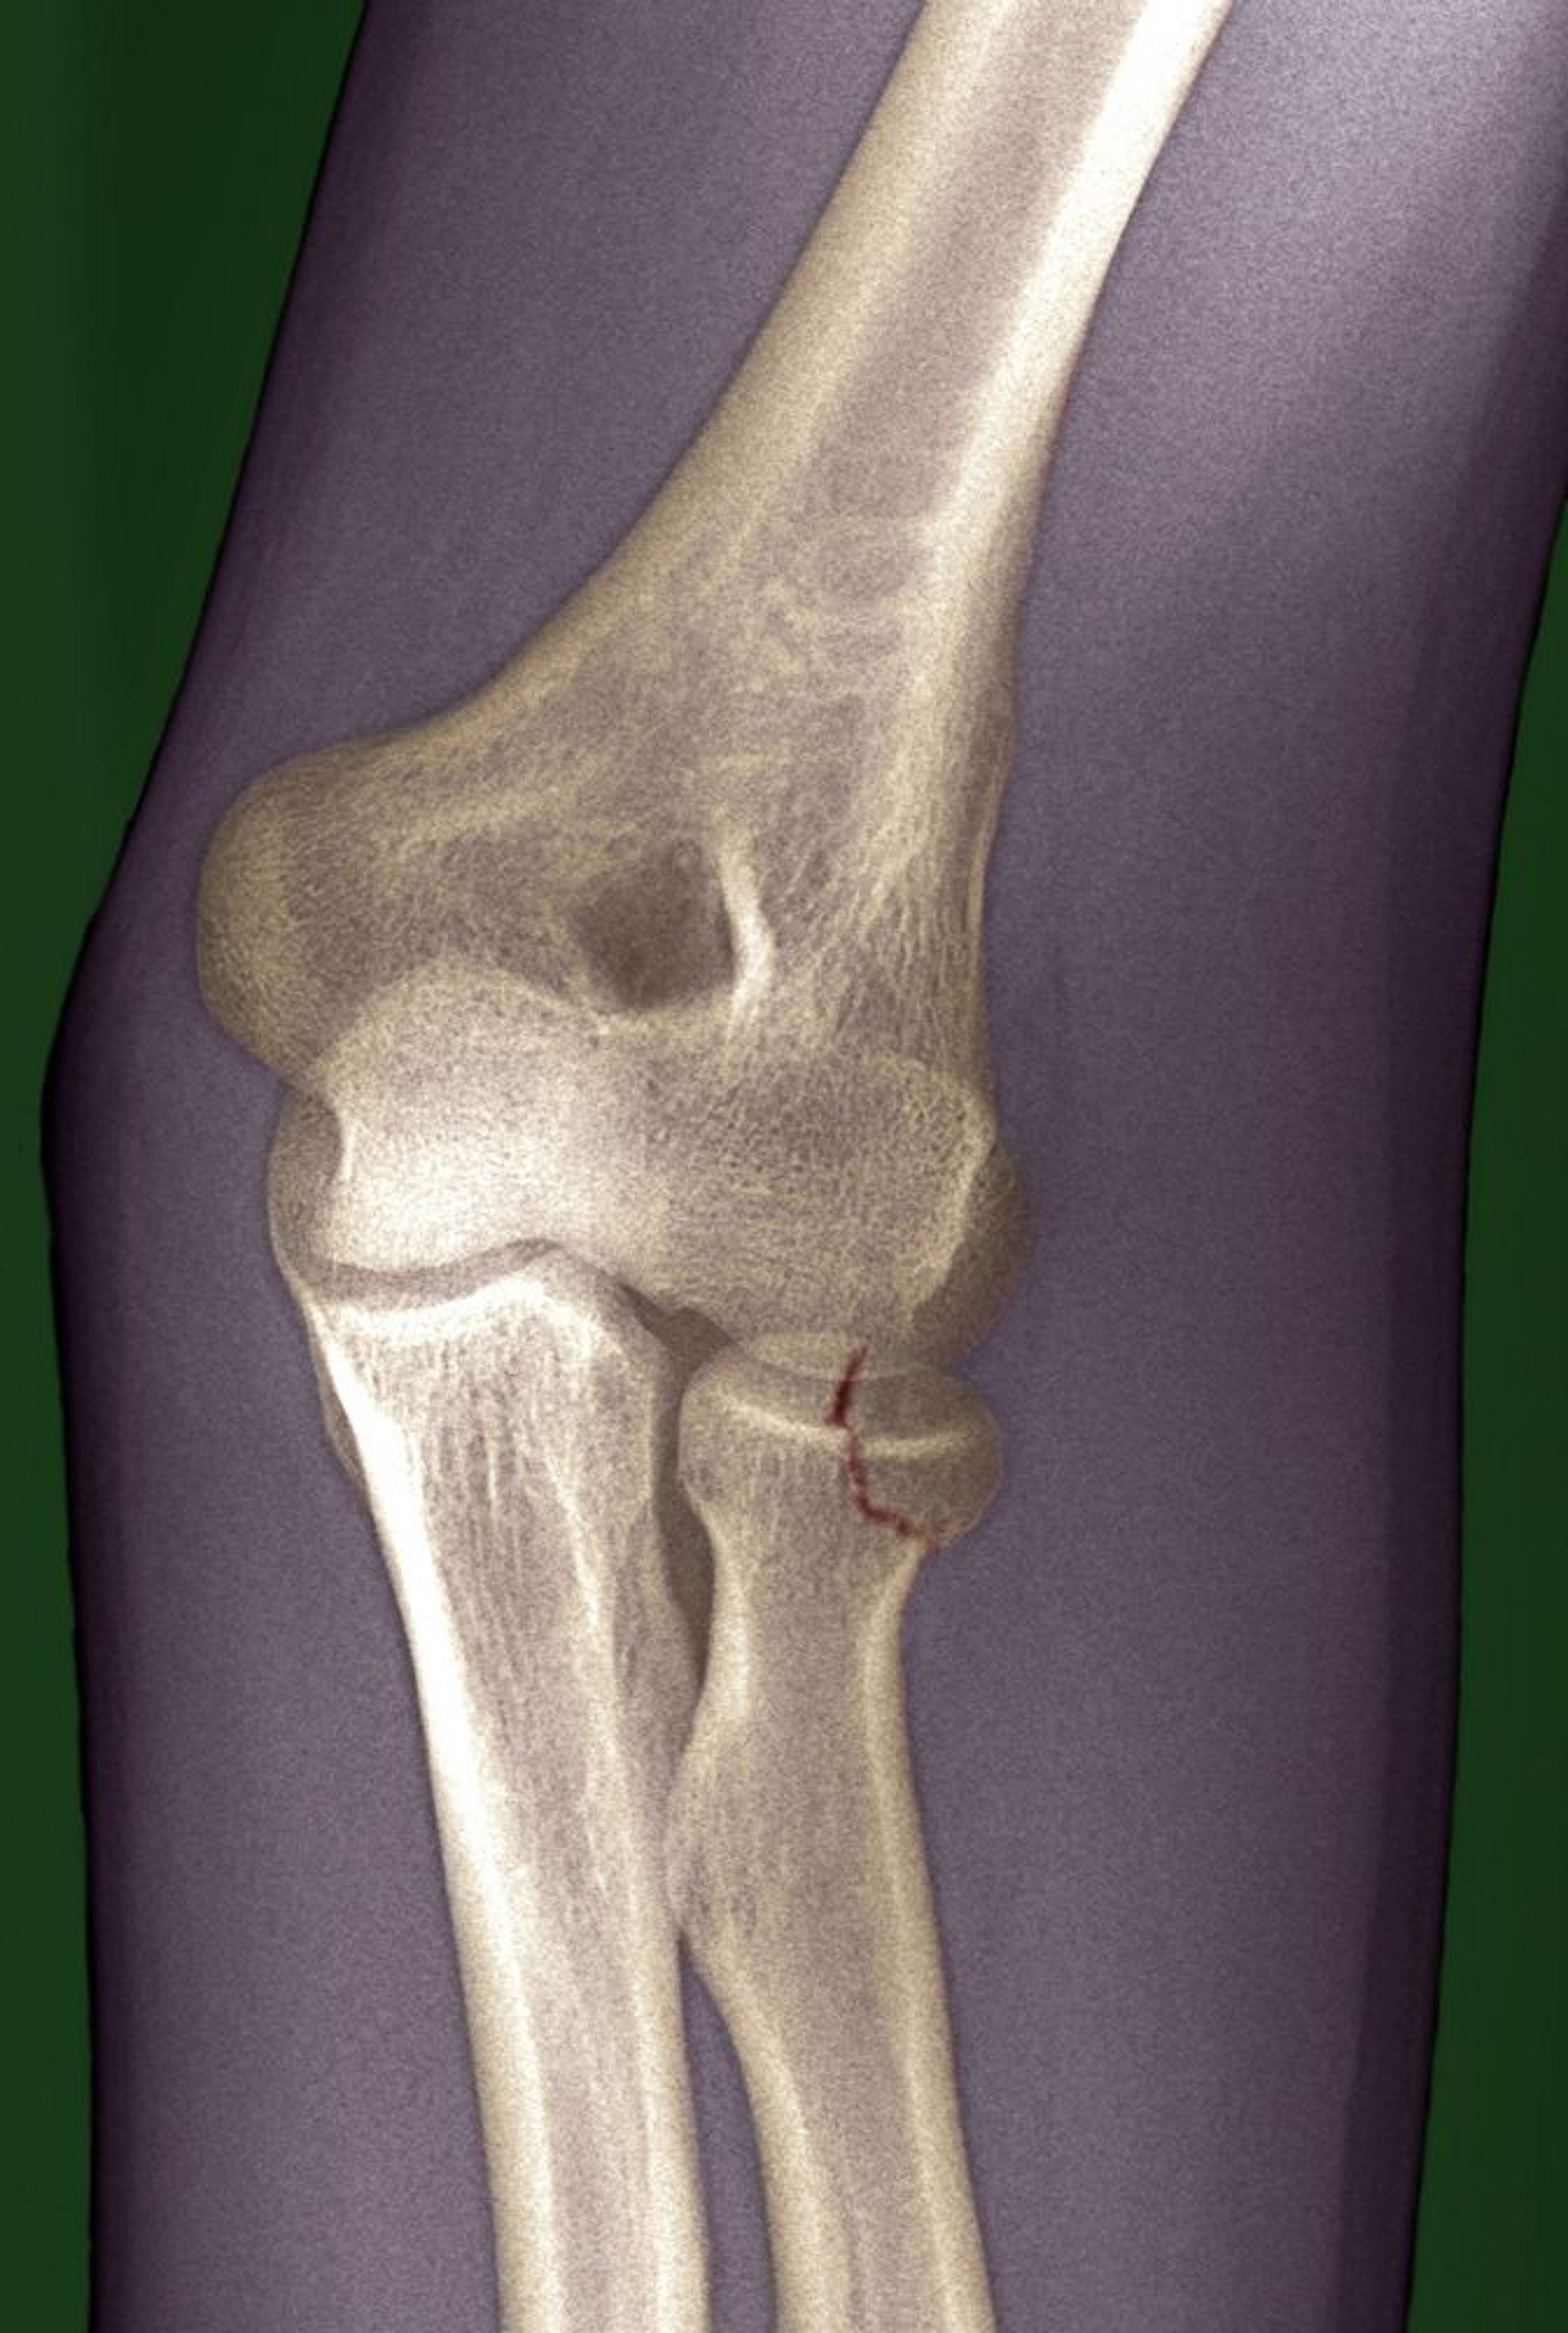

Fracture de la tête radiale

La ligne de fracture (marquée en rouge ici) est subtile et pourrait facilement être manquée.

DU CANE MEDICAL IMAGING LTD/SCIENCE PHOTO LIBRARY